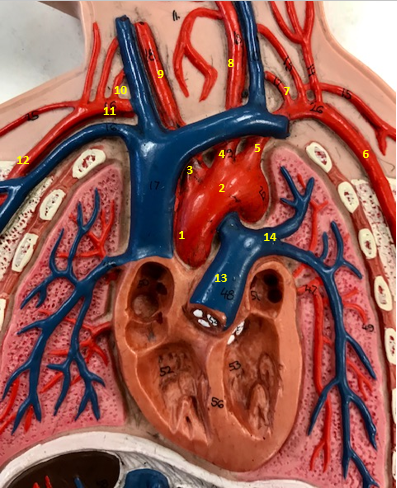

Aorta

Name #2

Brings blood out of left ventricle

Function of aorta

Brachiocephalic artery

Name #3

Supplies oxygenated blood to right arm shoulder neck and head

Function of brachiocephalic artery

Left common carotid artery

Name #4

Supplies oxygenated blood to left neck and head

Function of left common carotid artery

Left subclavian artery

Name #5

Supplies oxygenated blood to left arm shoulder

Function of left subclavian artery

Left axillery artery

Name #6

supplies blood to left armpit and upper limb

Function left axillary artery (6)

Left vertebral artery

Name #7

Supplies blood to brain and spinal cord

Function of left vertebral artery (7)

Left common carotid artery

Name #8

Supplies blood to left neck and head

Function of left common carotid artery (8)

Right common carotid artery

Name #9

Supplies oxygenated blood to right neck and head

Function of right common carotid artery (9)

Right vertebral artery

Name #10

Supplies blood to brain and spinal cord

Function of right vertebral artery (10)

Right subclavian artery

Name #11

Supplies blood to right arm and shoulder

Function of right subclavian artery

Right axillery artery

Name #12

Supplies blood to right armpit and upper limb

Function of right axillery artery (12)

Pulmonary trunk

Name #13

Bring blood out of right ventricle to lungs

Function of pulmonary trunk (13)

Left pulmonary artery

Name #14

Bring blood to left lung

Function of left pulmonary artery (14)